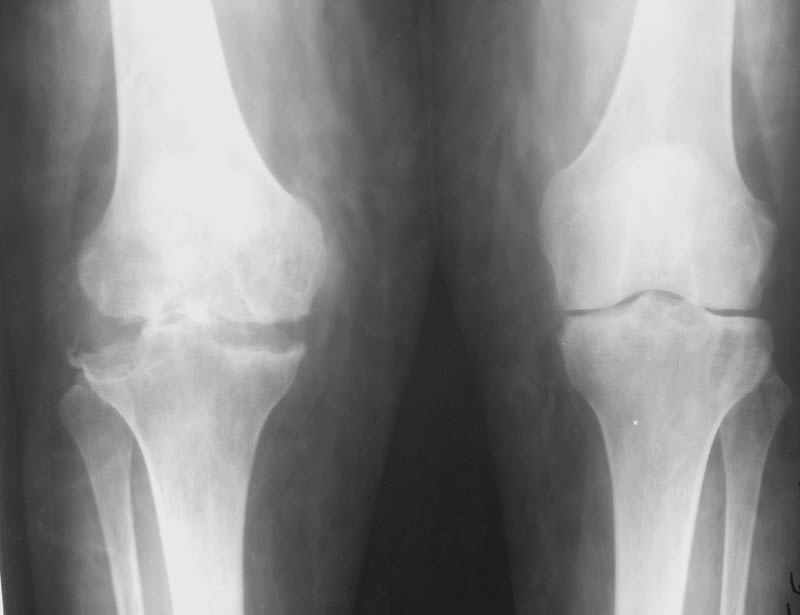

Использована цементная версия с пластикой дна впадины измельченной аутокостью и гранулами гидроксиапатита. Субъективное улучшение после операции. Улучшилось и стабилизировалось общее состояние. В настоящее время затруднено передвижение из-за поражения правого коленного сустава. Болезненный и <болтающийся> сустав. Предполагается замена сустава протезом без сохранения задней крестообразной связки. Возможные варианты? Заранее благодарю! С уважением,А.В.ВладзимирскийДонецкий НИИ травматологии и ортопедииДонецк, Украина

В случаях ревматоидного артрита с деструктивными изменениями сустава мы стараемся применять конструкции типа RT-Solution (Plus) или AGC (Biomet) из-за высокой вероятности нестабильности также и коллатеральных связок. Эти эндопротезы не требуют сохранения связок вообще. Выбор обусловлен также исходной вальгусной (варусной) деформации.